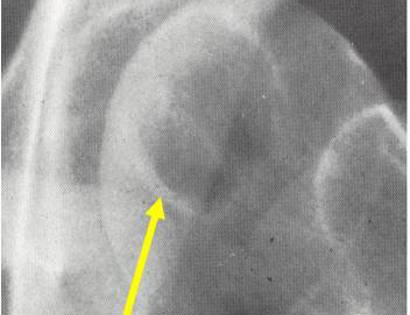

On an X-Ray, also called a radiograph, a clear cell chondrosarcoma can be diagnosed by looking at certain features. Most commonly seen in a clear cell chondrosarcoma is usually osteolytic, expansile lesion, that may be focally calcified, often a sharp interface between tumor and surrounding bone and the overlying cortex is usually thin, but intact.